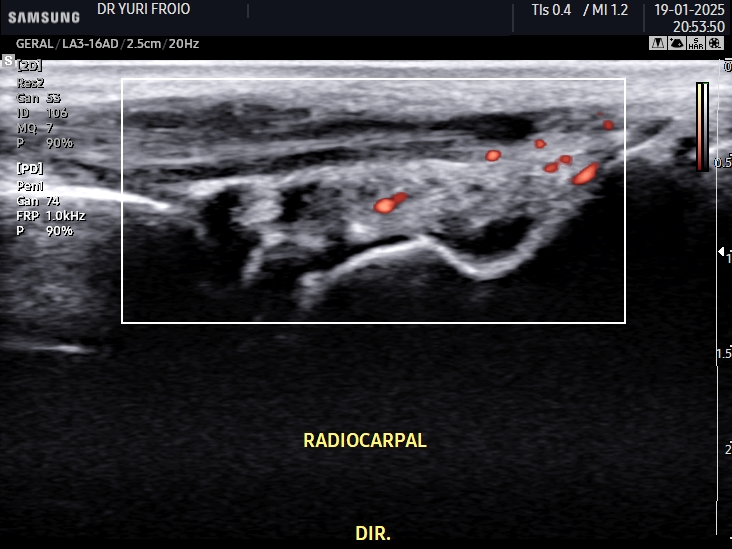

Diferente dos exames convencionais, como a radiografia, o ultrassom tem a vantagem de ser dinâmico, sem radiação e altamente sensível para detectar sinovite ativa, tenossinovite e entesopatias. A utilização do Doppler colorido e do Doppler de energia ainda permite avaliar o grau de atividade inflamatória, sendo um recurso valioso no manejo clínico.

Para padronizar a avaliação ultrassonográfica, foram desenvolvidos protocolos como o US7 e o US10. Eles visam uma abordagem estruturada e reprodutível para monitoramento das doenças reumáticas, especialmente a artrite reumatoide.